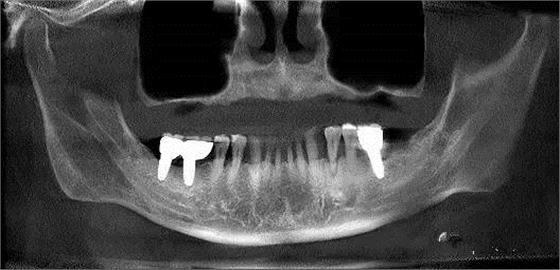

第三圖:上頜竇氣化導(dǎo)致上頜竇過大,上頜竇底骨質(zhì)向紙張一樣薄。只適合做外提升。